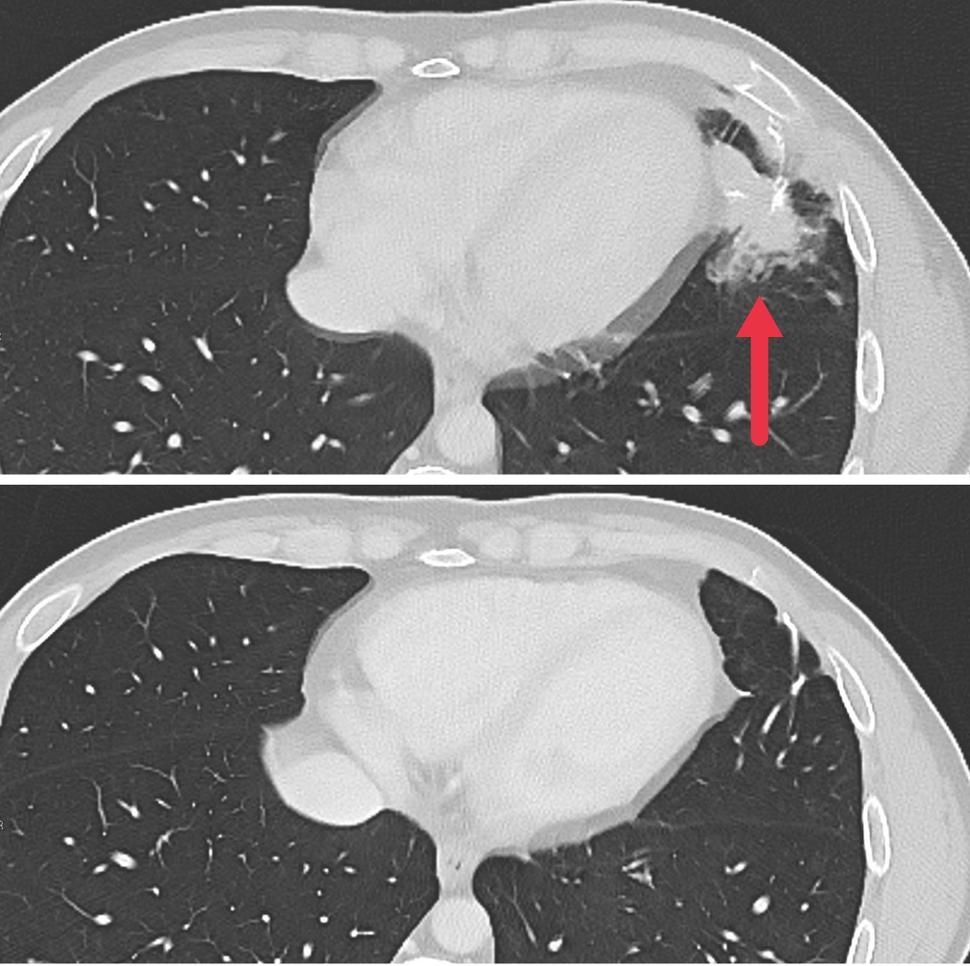

Cross-sectional CT images showing a metastatic tumor in the left lung of a patient (top image) and no tumor following treatment (bottom image).

As part of a larger phase 2 trial, seven patients with metastatic colon cancer were treated with the experimental personalized cellular immunotherapy. All seven received several doses of the immunotherapy drug pembrolizumab (Keytruda) before the cell therapy and another immunotherapy drug called IL-2 afterward. Three patients had substantial shrinkage of metastatic tumors in the liver, lung, and lymph nodes that lasted for four to seven months. The median time to disease progression was 4.6 months.